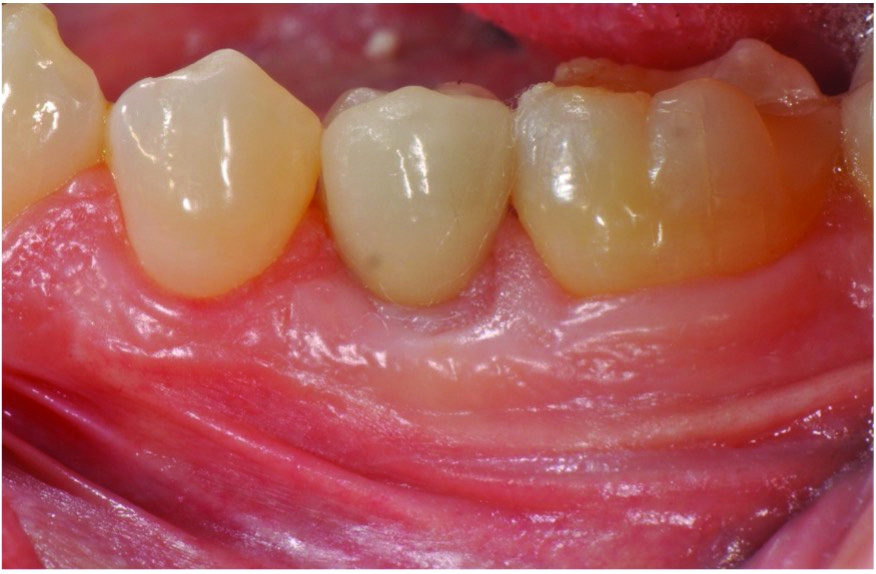

A postsurgical periapical x-ray was taken (Figure 9). Postoperative visits were at 2- to 3-week intervals. The patient was instructed to use chlorhexidine for 2 weeks, followed by the use of a two-row soft toothbrush and interproximal flossing. Interproximal proxy brush usage began after the suture removal at 4 weeks. After 2 months, healing was excellent (Figure 10); at 9 months, the interproximal papillae regeneration was complete, and radiographic confirmation of radiographic intrabony defect fill was observed (Figure 11 and Figure 12). After 1 year, maintenance visits were conducted by the restorative office's registered dental hygienist.

Fig 10. Clinical presentation at 2-month follow-up.

Figure 10